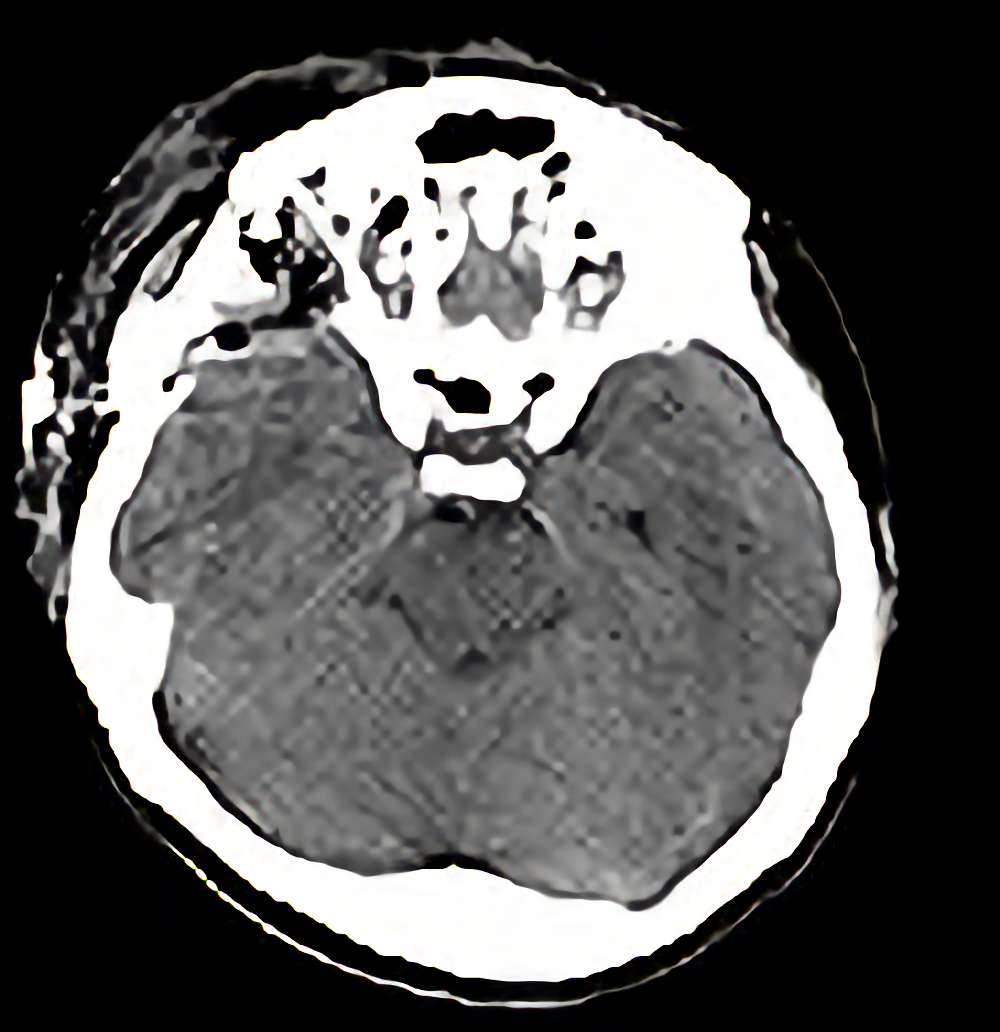

症例 '13年1月

No.

年_番号

手術年月

患者年齢

’13_3

'13年1月

30代

病名

術式

備考

頭蓋底腫瘍

断層撮影

手術前

1

手術前2

手術後